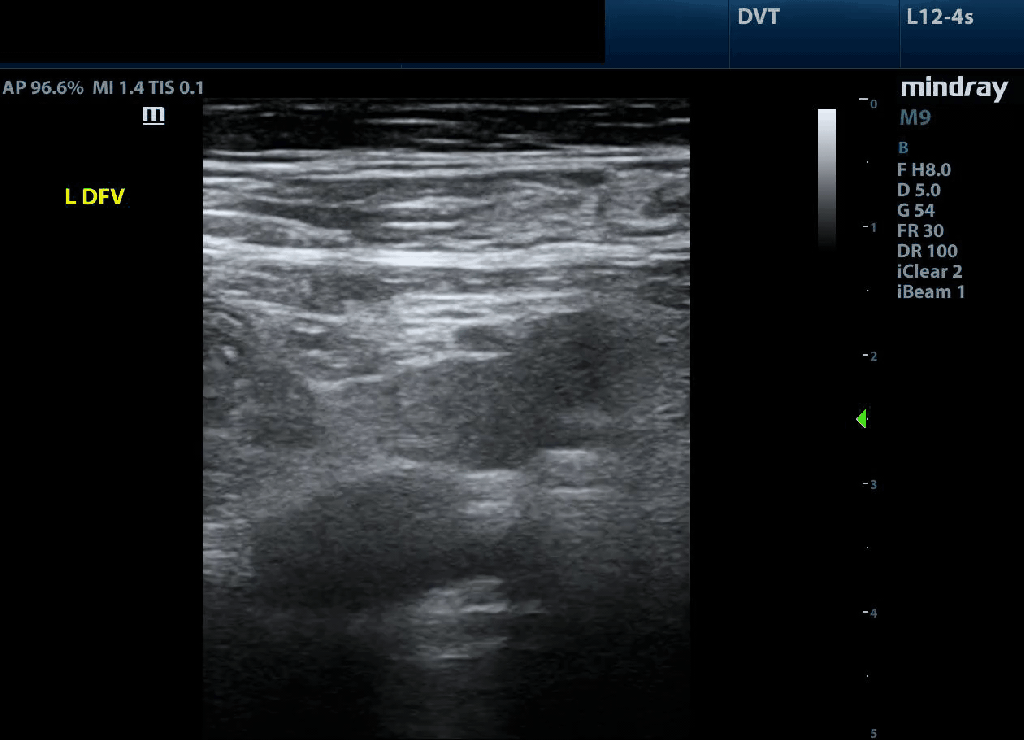

Indeterminate: In this clip we do not see compression of the femoral vein or deep femoral vein but we cannot easily visualize a clot either. There is significant longitudinal shifting caudally of the probe evidenced by the branch point to the deep femoral vein coming into view midway through the clip. Lack of compressibility is most often due to inadequate compression BUT a very acute clot (which can be completely anechoic) cannot be excluded. In this scenario a comprehensive radiology exam is mandated as a next step to resolve this if optimization of positioning and compression maneuver does not help.